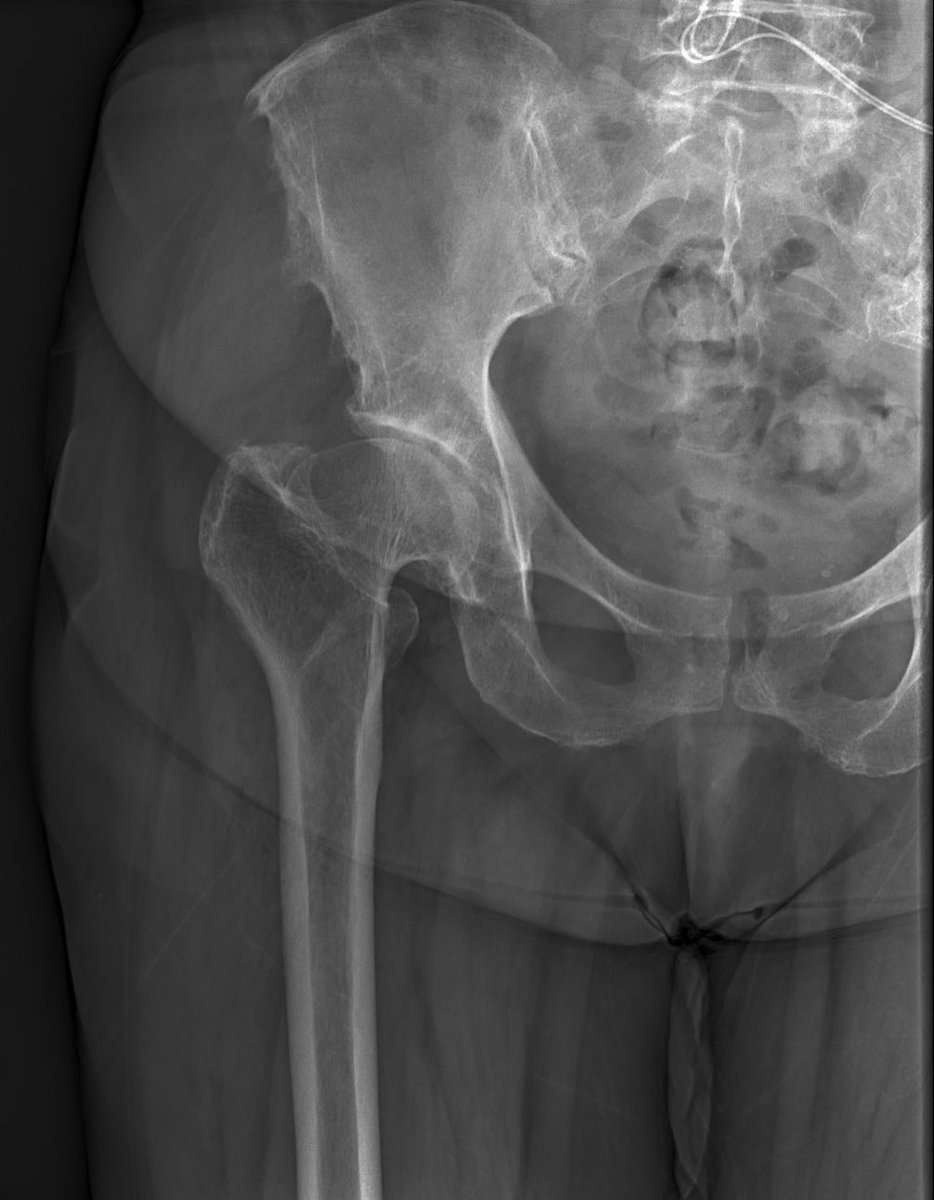

Female 67 y/o - THA

*Approach?

*What stem do you choose?

*Comments & tricks?

@AAHKS_YAG @AAHKS_YAG @JArthroplasty @AAOS1 @CleClinicArthGp